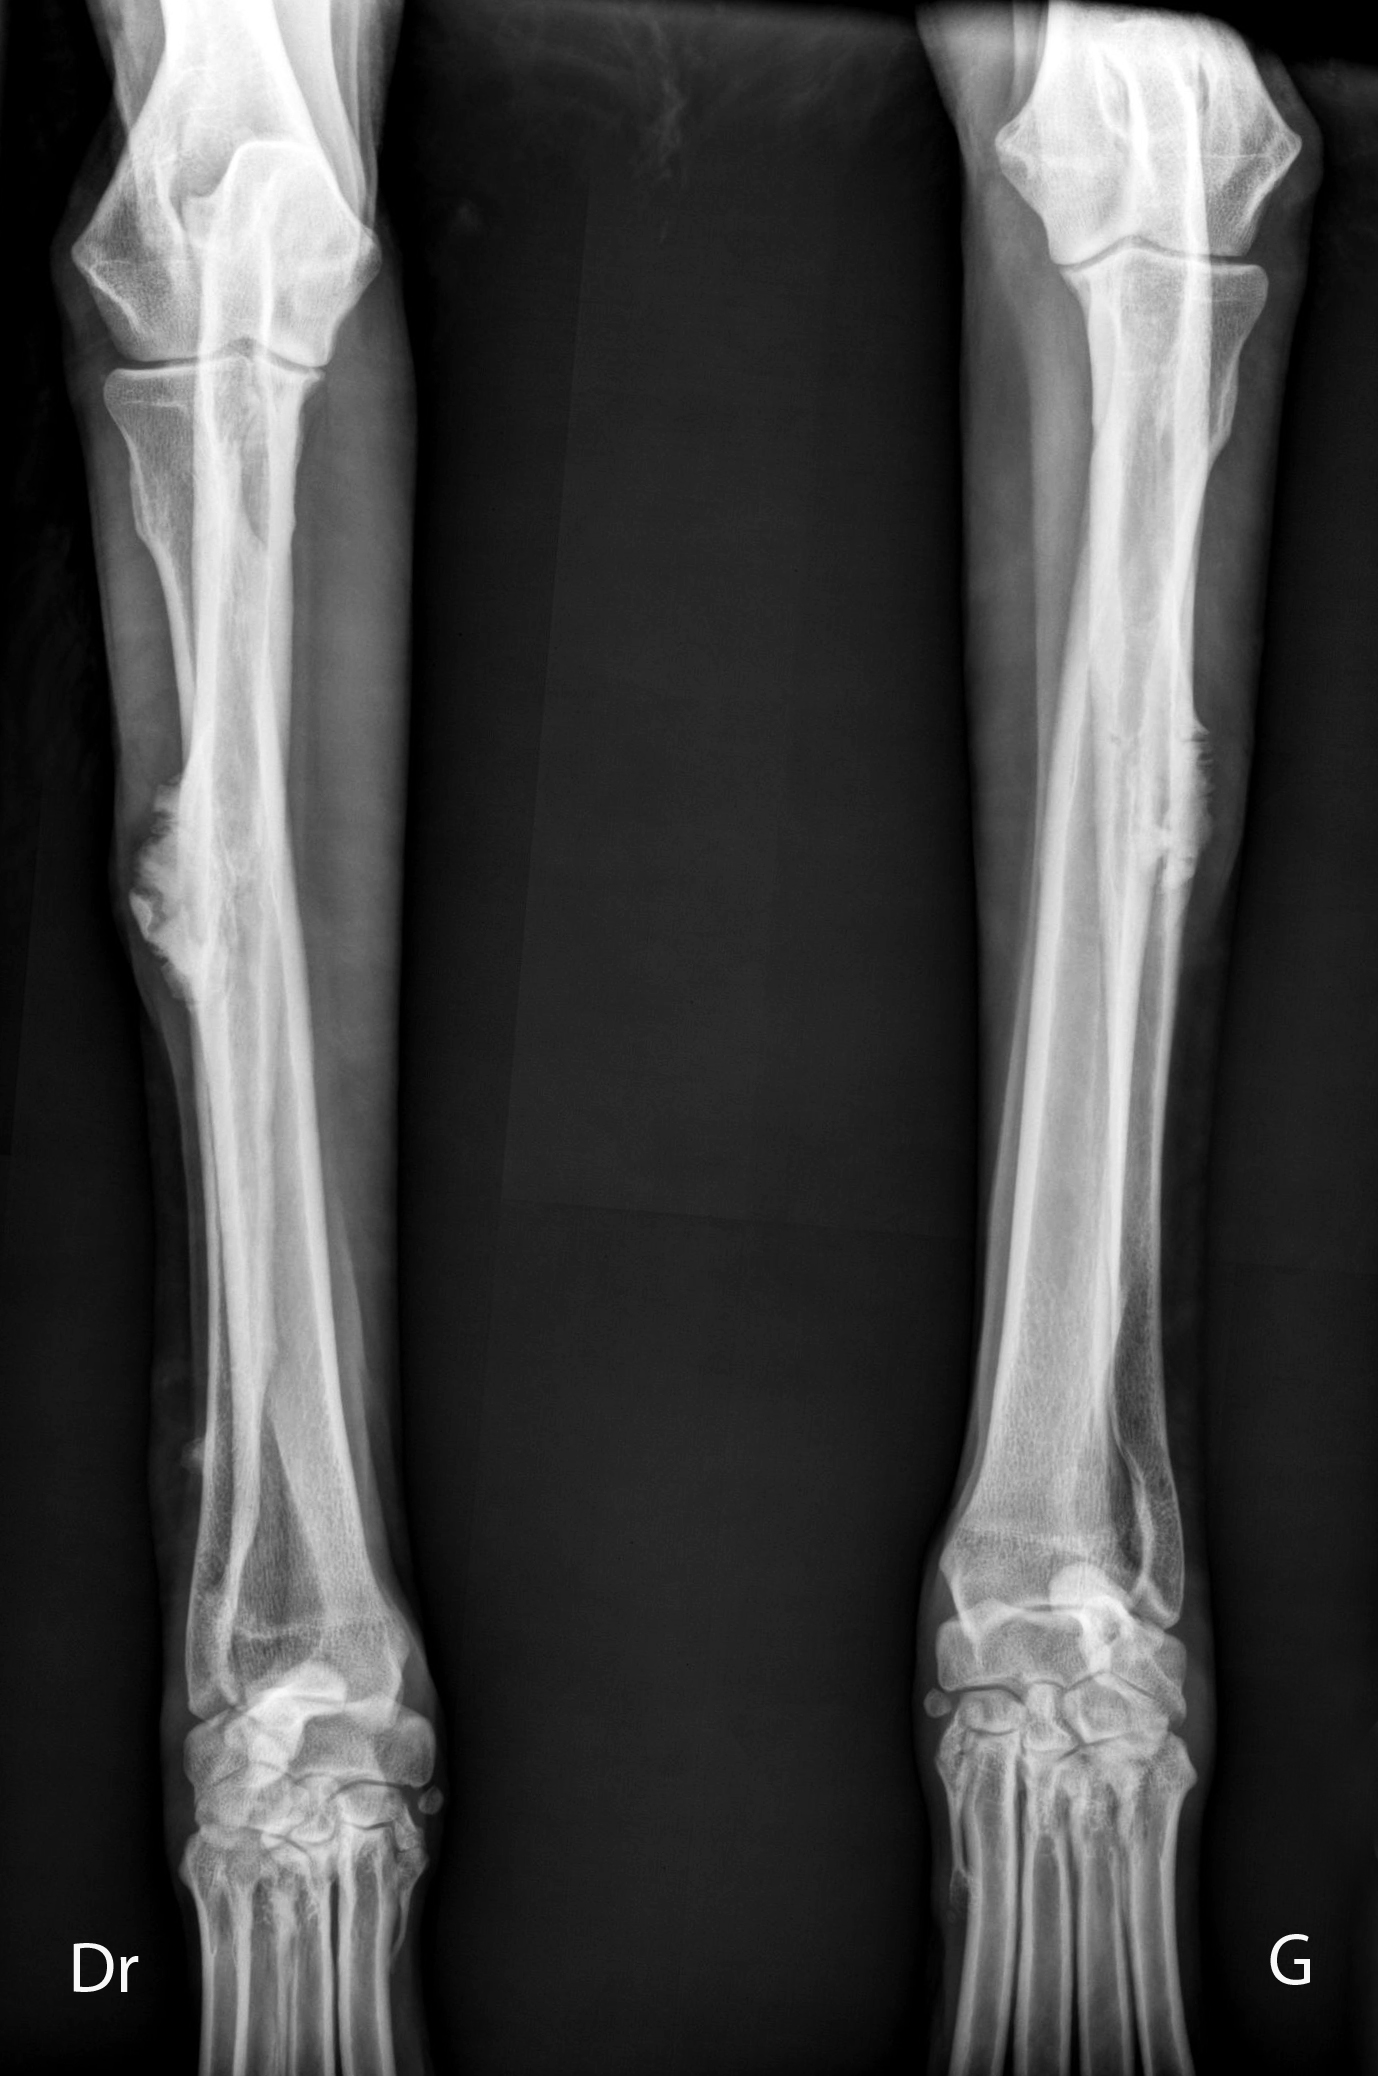

Crâniocaudale